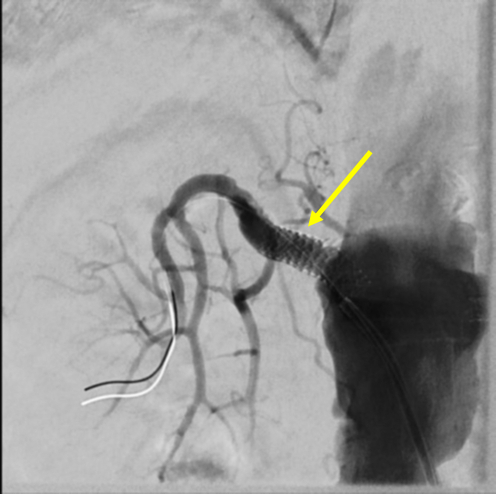

The patient was initially treated with non-invasive ventilation, a continuous nitroglycerin infusion, and IV furosemide with rapid improvement in her symptoms and vital signs. She was quickly transitioned to simple nasal cannula and oral antihypertensive medications; IV diuresis was continued. However, despite these initial improvements, her renal function steadily worsened over the subsequent days. Renal doppler ultrasound revealed an elevated right renal artery peak systolic velocity of 292 cm/sec with delayed acceleration times. After an interdisciplinary discussion, she underwent right renal artery angiography and drug-eluting stent placement.

Post-procedural renal doppler ultrasound showed an improvement in right-sided PSV to 137 cm/sec with no evidence of RAS. Post-discharge blood pressures remained improved and her renal injury resolved with no further hospitalizations after six months.